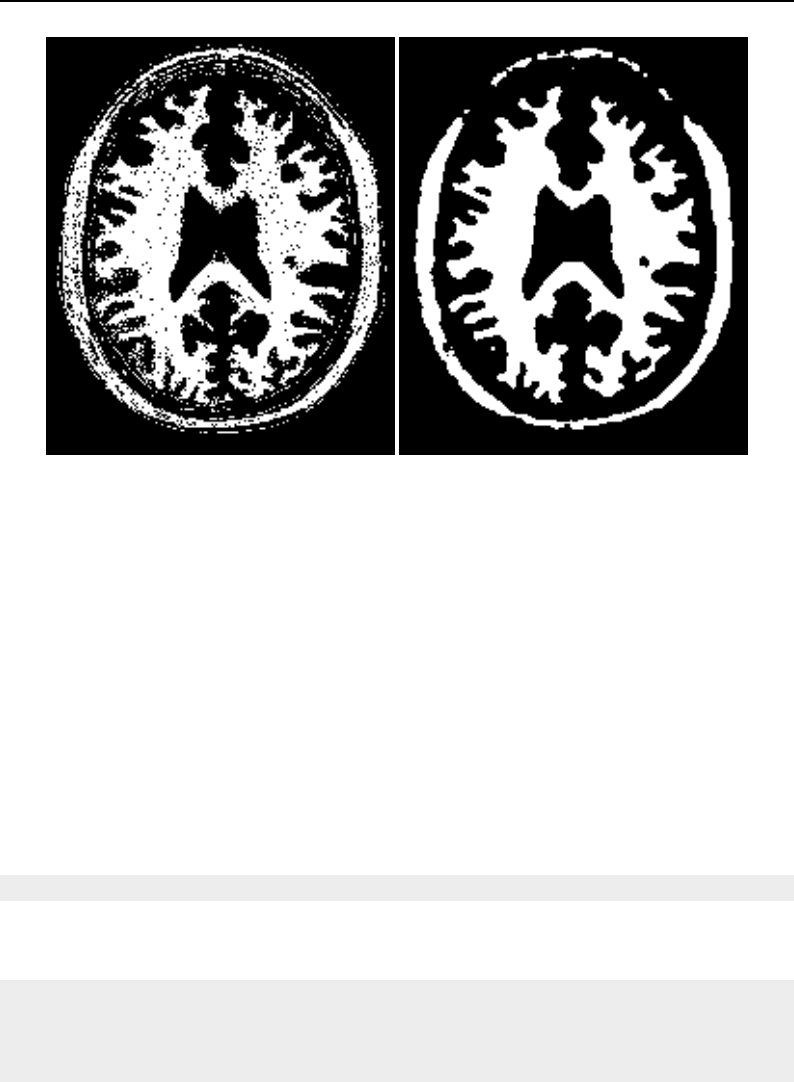

The Insight Toolkit (ITK) is an open-source, cross-platform system for medical image processing. It

provides medical imaging researchers with an extensive suite of leading-edge algorithms for

registering, segmenting, analyzing, and quantifying medical data. It is used in thousands of research

and commercial applications, from major labs to individual innovators.

The National Library of Medicine Insight Segmentation and Registration Toolkit, shortened as the

Insight Toolkit (ITK), is an open-source software toolkit for performing registration and segmenta-

tion. Segmentation is the process of identifying and classifying data found in a digitally sampled

representation. Typically the sampled representation is an image acquired from such medical instru-

mentation as CT or MRI scanners. Registration is the task of aligning or developing correspondences

between data. For example, in the medical environment, a CT scan may be aligned with a MRI scan

in order to combine the information contained in both.